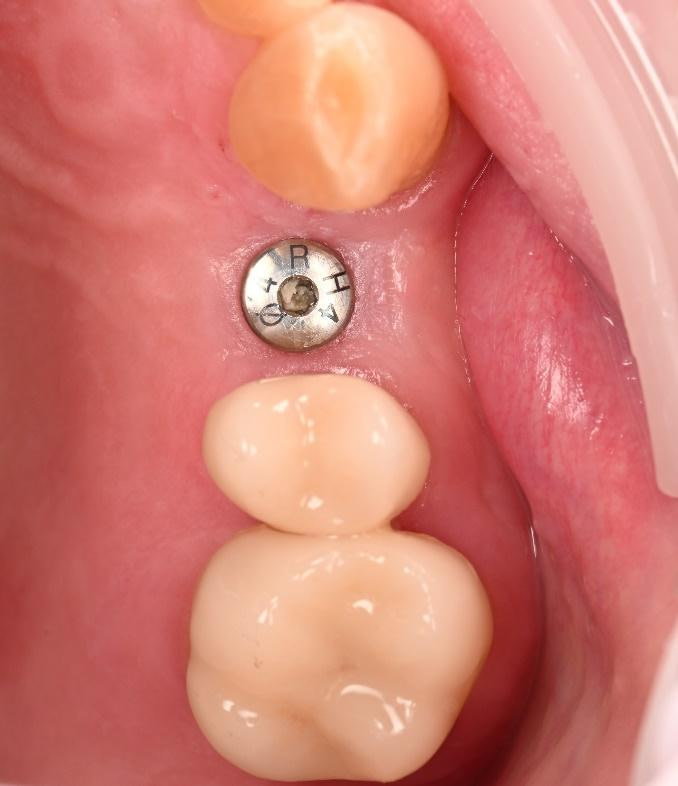

Three months after the implant surgery, a thorough post-operative assessment revealed excellent healing and implant stability.

Digital impressions were captured using the TRIOS 4 intraoral scanner, and the implant-supported crown was designed using 3Shape Design Studio.

At the final appointment, the crown was securely attached to the implant, resulting in a beautiful, natural-looking restoration.

The implant-supported crown seamlessly integrated with the patient's natural dentition, and the patient reported excellent comfort and function.